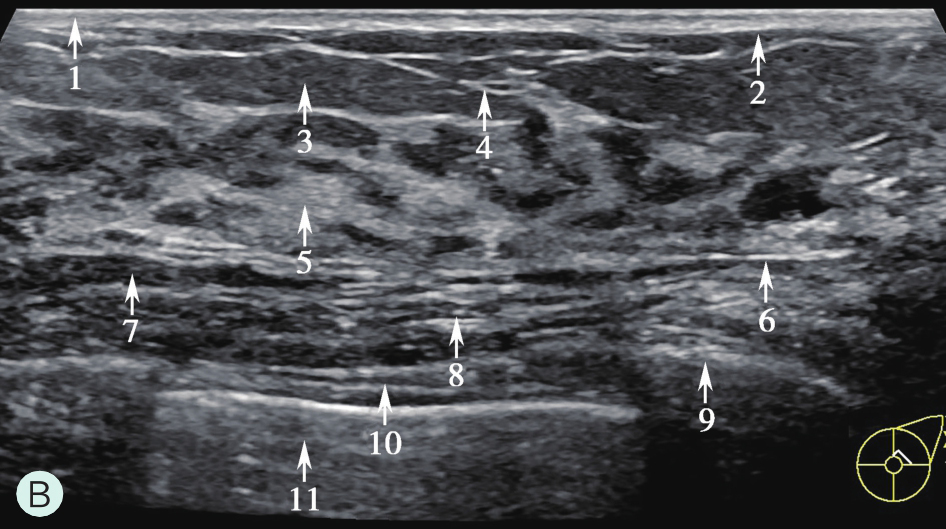

图1-1-1 乳腺腺体及周围组织图

1.皮肤及皮下组织;2.浅层浅筋膜;3.脂肪;4.Cooper韧带;5.乳腺腺体;6.深层浅筋膜;7.乳房后间隙;8.胸大肌;9.肋骨;10.肋间肌;11.胸腔及肺组织